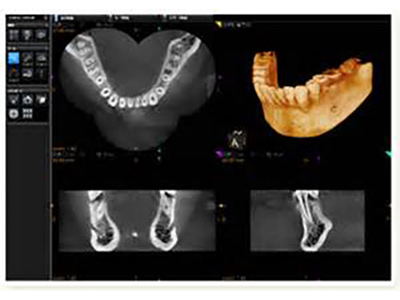

当院ではCTを設置しております。一般的なレントゲンでは、奥行きや細かい像を確認できないため、CTを用いて

三次元画像による診断を行います。インプラントだけではなく、様々な治療に使用します。

インプラント治療や、埋もれている歯の抜歯、口腔内の手術などを行う場合には、まずコンピューターでシミュレーションを行います。

CT画像をノーベルクリニシャン®︎で処理することで、様々な角度から画像を分析することが可能です。ノーベルクリニシャン®︎を使用する事で、より安全な治療が可能となりました。